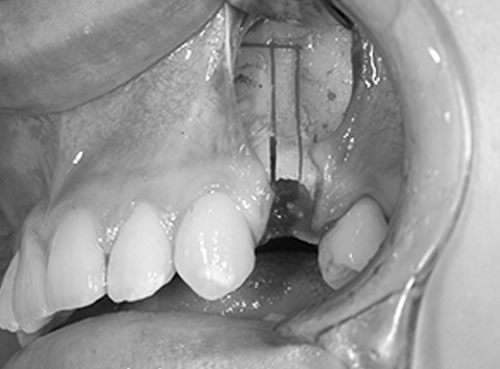

13. 骨を固定します

口ごぼ改善のための、見た目とかみ合わせが理想の形に整ったら、骨を固定します。固定材料には、溶けるプレート、チタン製のプレート、ステンレス製のワイヤーがあります。どれを使うかは、手術中の骨の安定感や調整の多い、少ないなど状況に応じて使い分けます。

10. 後ろに下げた骨を固定します

見た目の調整が終わり、かみ合わせも良くなったら、その位置に下あごの骨を固定します。後ろに下げた上のあごの位置に合わせます。

固定する材料は、チタン製のプレート、骨接合用ステンレス製のワイヤー(矯正用のワイヤーとは違います。)、溶けるプレートがあります。どの固定材料を使うかは、上と下のかみ合わせ具合や、お鼻やあご先とのバランス、手術中の骨の安定感や調整の程度など状況に応じて使い分けます。